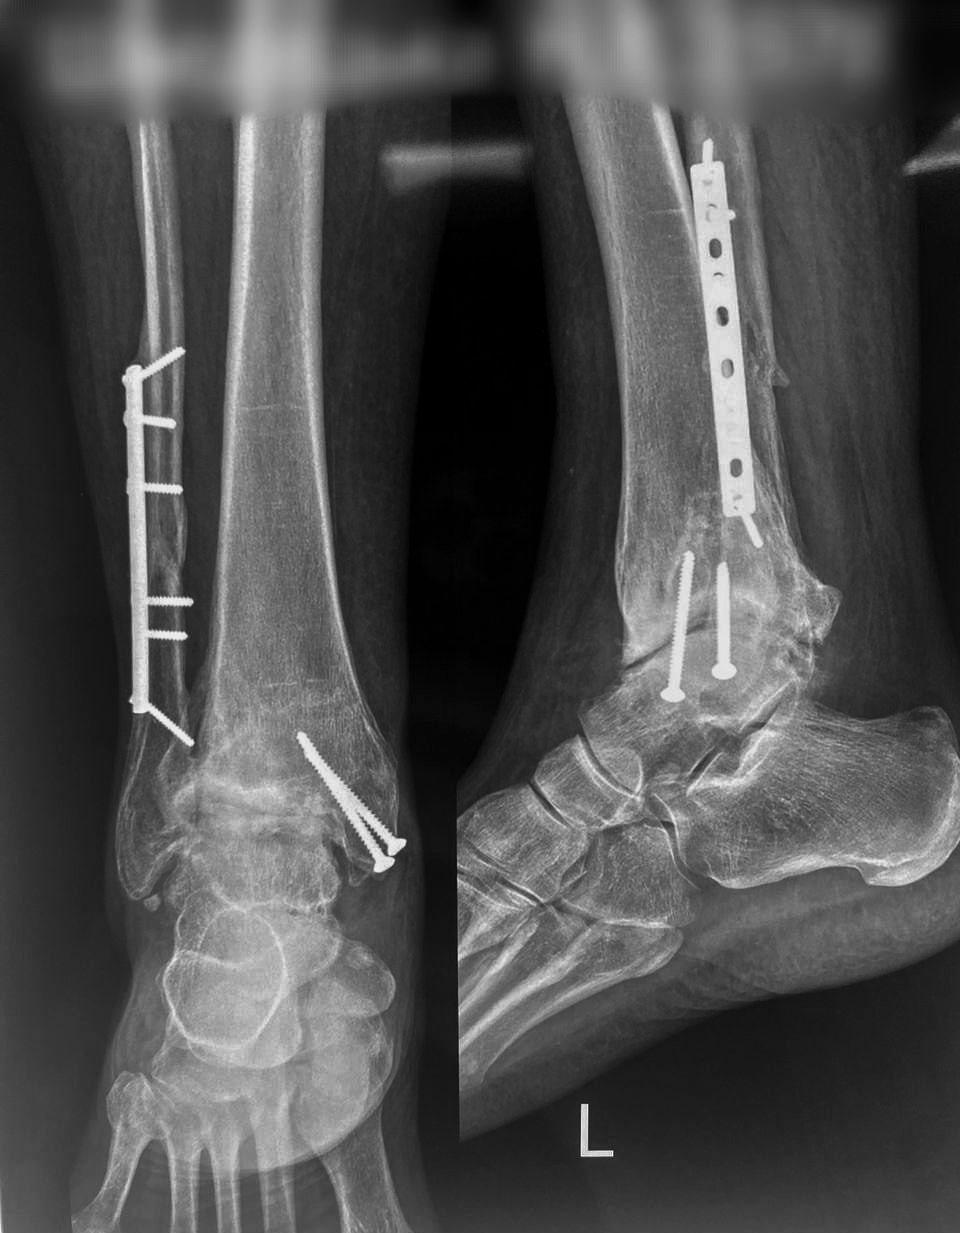

Перелом пілона: приклад на зображенні

На зображенні вище ви можете бачити приклад перелому пілона, поєднаного із переломом малогомілкової кістки вище синдесмозу (перелом Мезонева).

Внутрішня фіксація пластинами та гвинтами: приклад